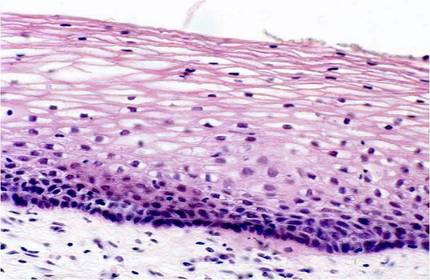

Tejido Epitelial de revestimiento, Epitelio de Transición (Urotelio)